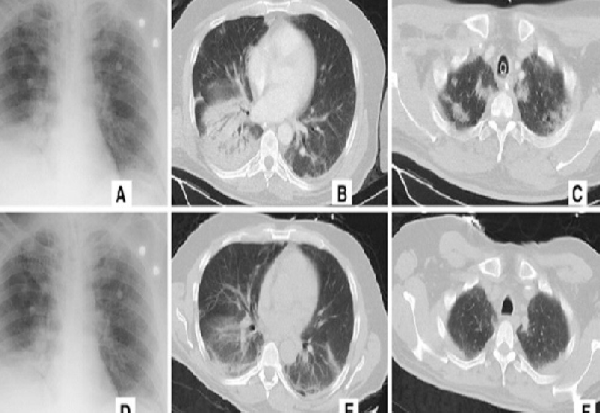

„Алибаба“ тврди дека новиот систем може да открие коронавирус со помош на скеновите од компјутерската томографија на градите на пациентите со 96 отсто точност. Потребни се само 20 секунди за вештачката интелигенција да постави дијагноза. Според извештајот, на луѓето им се потребни околу 15 минути за да ја дијагностицираат болеста бидејќи може да има над 300 слики за процена.

Системот тренирал на слики и податоци од 5.000 потврдени случаи на коронавирус и веќе е тестиран во болниците низ цела Кина. Најмалку 100 здравствени установи во моментот работат со вештачката интелигенција на „Алибаба“.